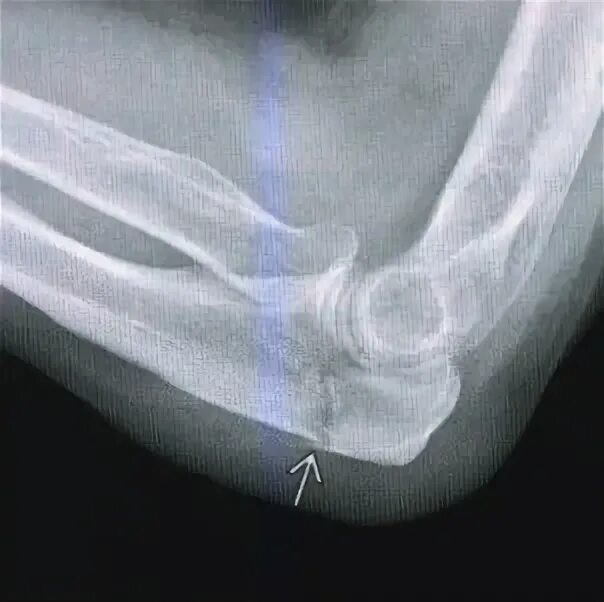

Перелом локтевой сустав мкб 10